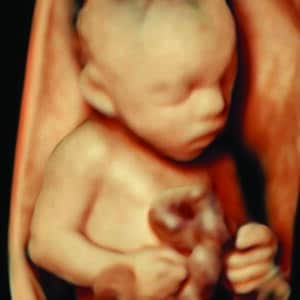

Explore our Photo Gallery and see the real results from Knit 4D Ultrasound. Every image you see  from 2D, 3D, 4D, to HD live ultrasounds  was captured by our highly trained team using our state-of-the-art ultrasound machine. We can begin creating amazing 3D/4D keepsake images as early as 8 weeks, giving you a beautiful first look at your baby.